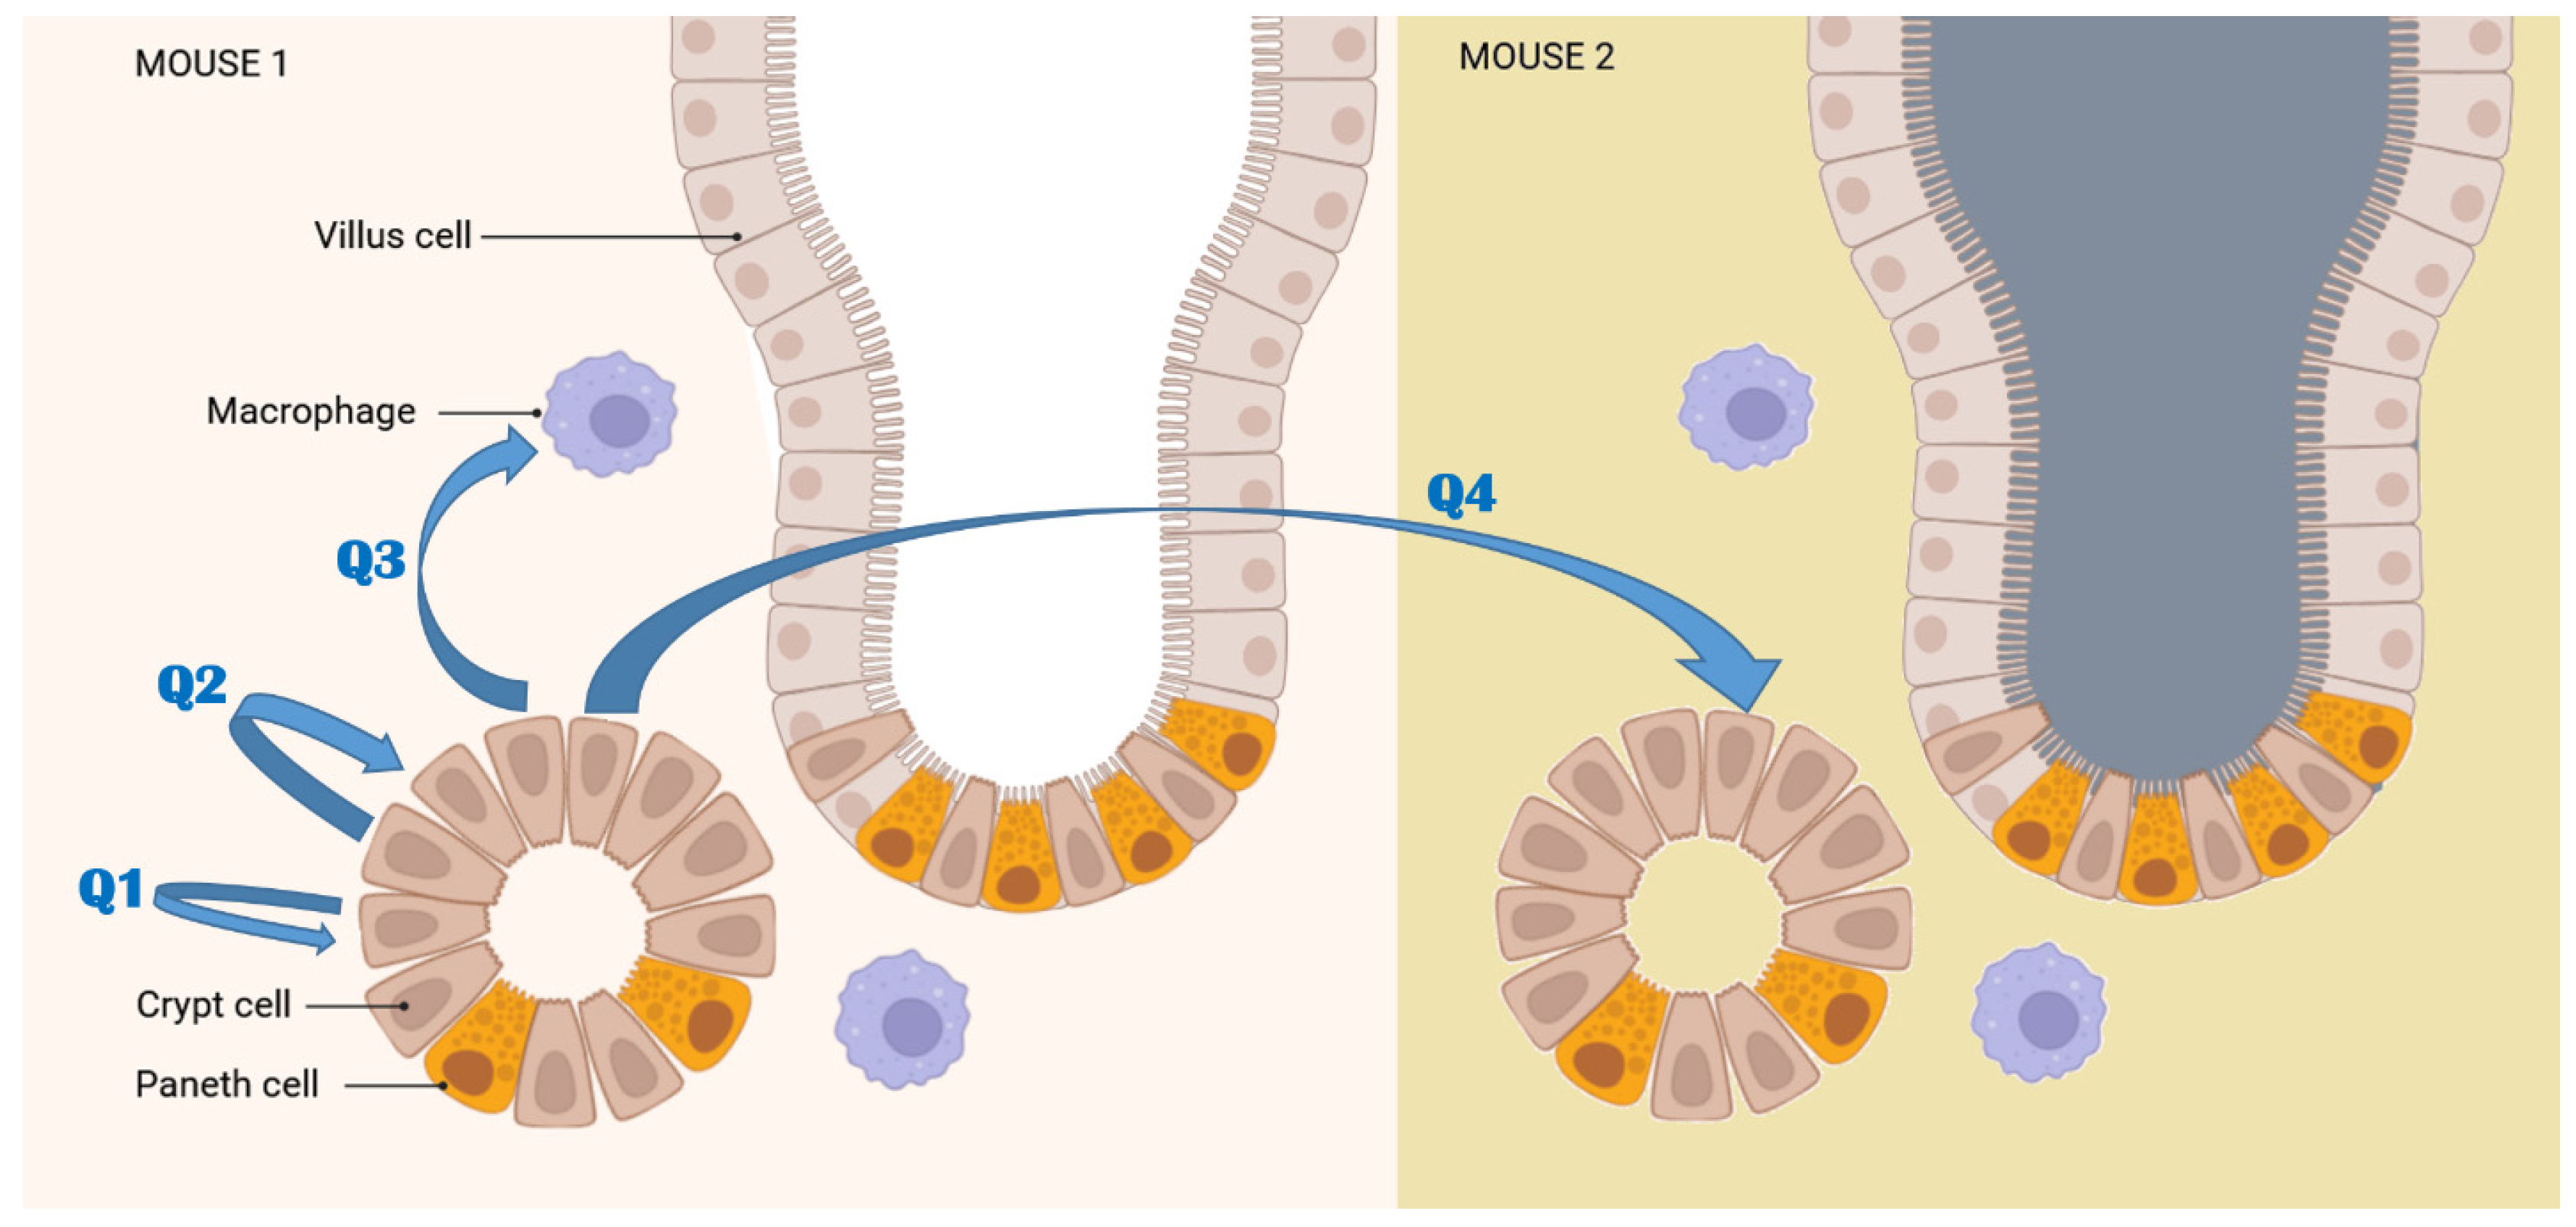

:1. Introduction

2. Results

2.1. Elemental Maps of Control and Irradiated Mouse Intestine Samples

4. Materials and Methods